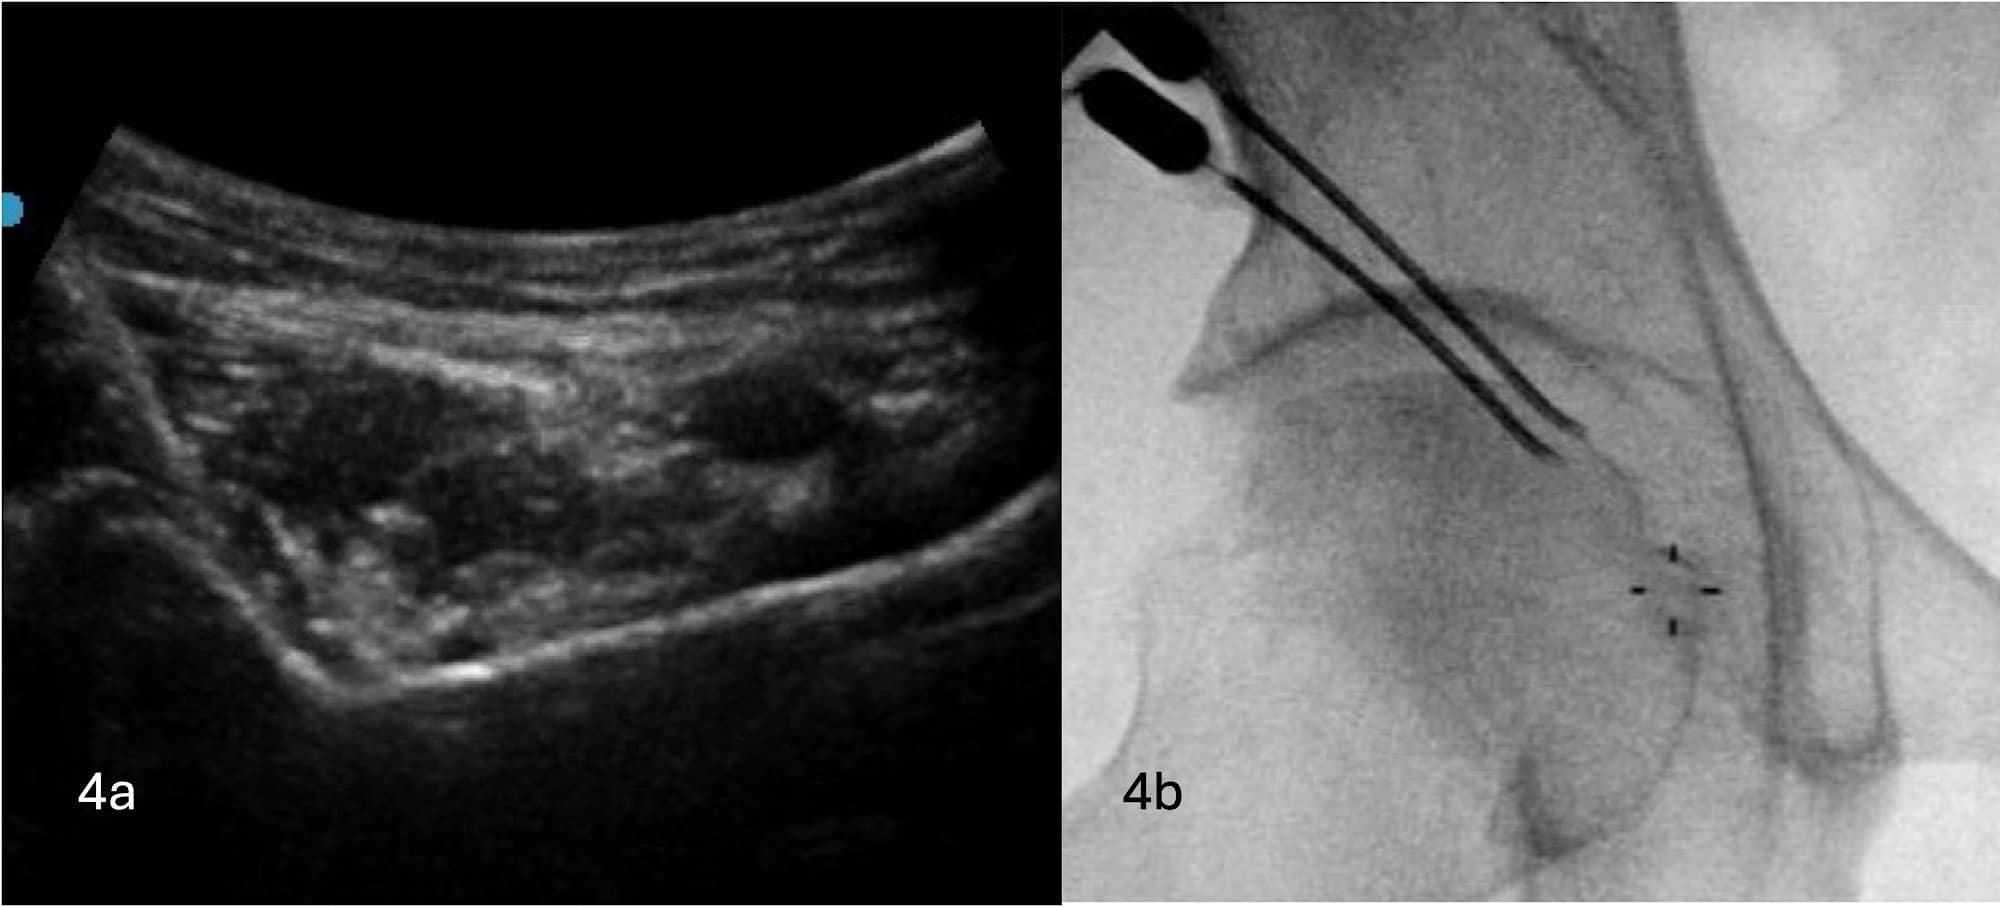

For the articular branches of the femoral nerve and accessory obturator nerve, the RF cannula is inserted under ultrasound guidance from lateral to medial with modest cephalad to caudad angulation from the AIIS to the IPE at an overall angulation corresponding to the bony descent. The RF cannula is placed with the tip deep to the psoas tendon or medial, bypassing the psoas tendon with continuous ultrasound guidance. A larger lesion is preferred to ensure capture of the target nerves due to the variable innervation patterns of the anterior capsule.9 The author HM typically uses a bipolar approach, and therefore, a second RF cannula is inserted just cephalad to the first cannula along the IPE. The author AM uses a cooled radiofrequency ablation technique.

Once the RF cannulas have been brought into contact with IPE, fine-tuning the cannula's position under fluoroscopic guidance is performed to ensure optimal placement of RF cannulas to one another (see Figures 4A and 4B).